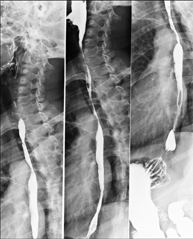

Tècnica que usa els raigs X a través de la qual s'obtenen imatges de la columna dorsal per al seu estudi. Indicacions: traumatisme, dolor, escoliosi. - Esofagograma

Prova diagnòstica que consisteix en obtenir imatges radiològiques en moviment de l'esòfag mitjançant l'ús de raigs X (fluorosòpia) i d'un contrast opac baritat que s'administra per via oral.

- Spinal teleradiology

This technique uses X-ray rendered imaging to examine the entire spinal column, especially assessing the presence of scoliosis and pelvic dysmetria.